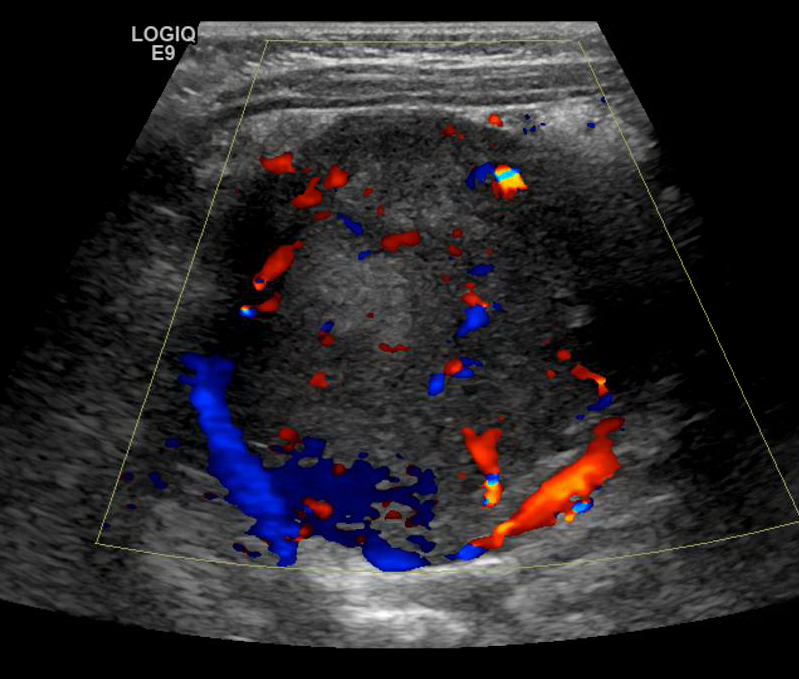

Neuroblastoma encasing the Aorta, SMA and Celiac artery